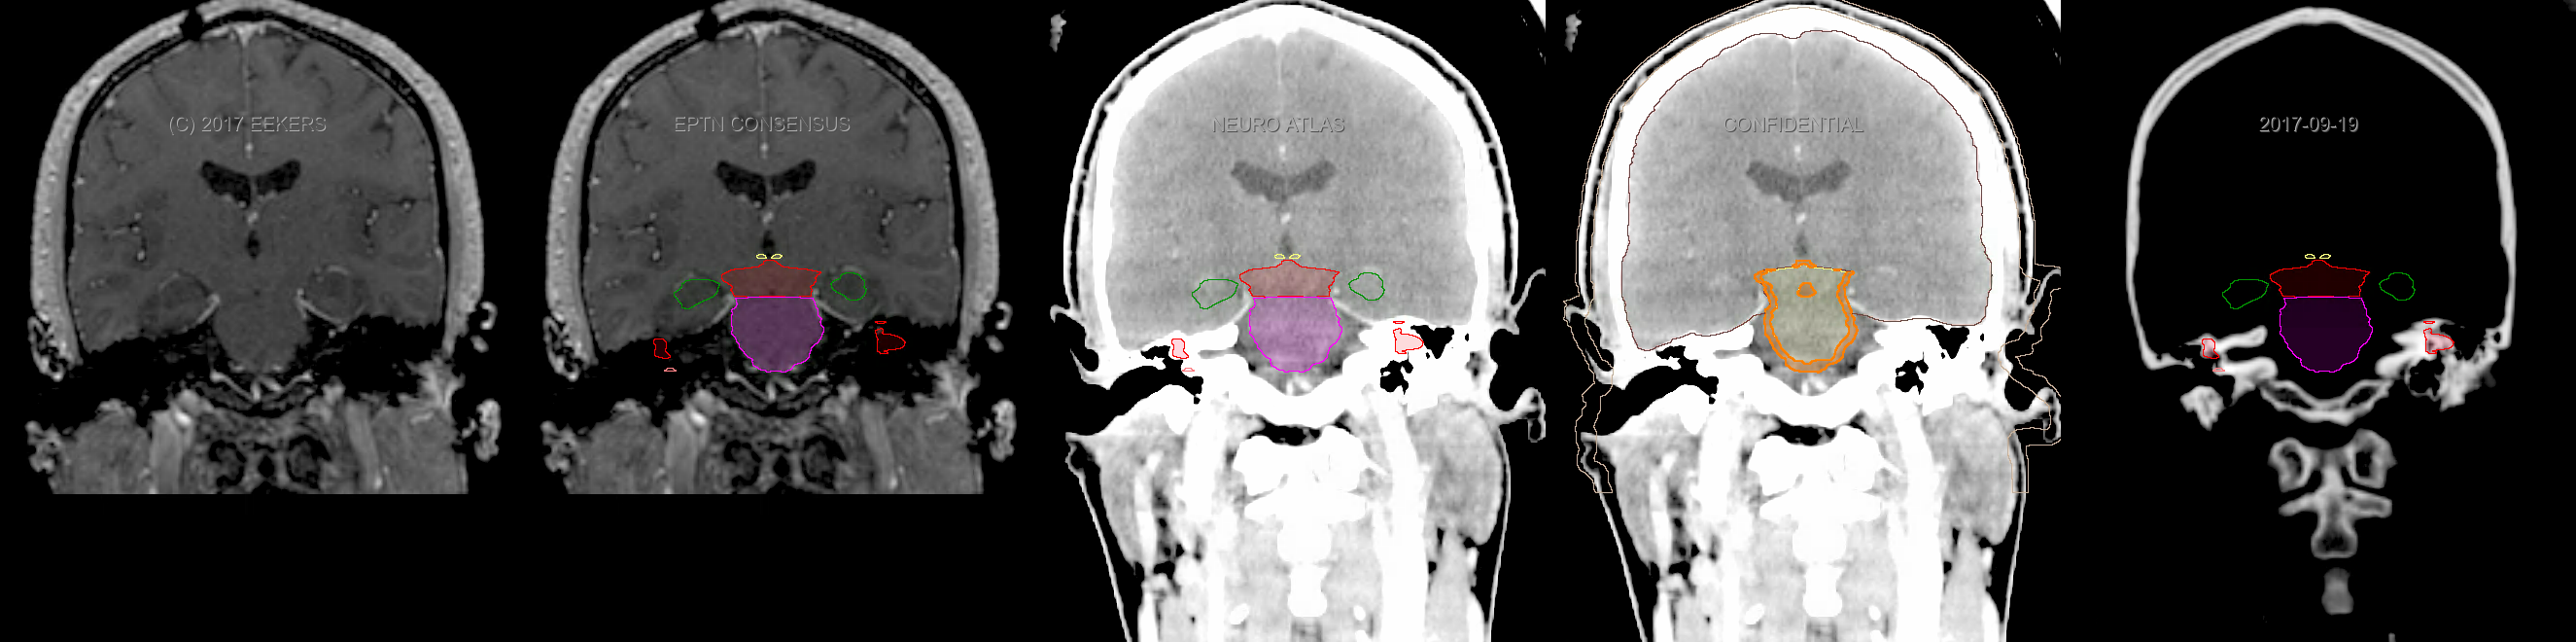

Three-dimensional delineation of the fifteen consensus OARs for neuro-oncology are shown on CT and 3 Tesla (3T) MR images (slice thickness 1 mm with intravenous contrast agent). All are presented in transversal, sagittal and coronal view.

From left to right: MR without structures, MR with structures, CT (WW/WL 120/40) with structures, CT (WW/WL 120/40) with Brain and Brainstem Surface, CT (WW/WL 1500/120)with structures